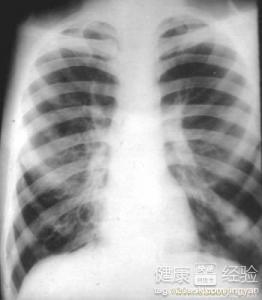

支氣管炎是一種常見(jiàn)的呼吸系統(tǒng)疾病,其癥狀包括咳嗽、咳痰、呼吸急促等,許多患者關(guān)心的問(wèn)題是:支氣管炎能自愈嗎?本文將詳細(xì)解析支氣管炎的類型、癥狀、治療方法以及能否自愈的問(wèn)題,幫助患者更好地了解并應(yīng)對(duì)這一疾病。

支氣管炎是指氣管、支氣管黏膜及其周圍組織的炎癥,根據(jù)其發(fā)病的急緩,可分為急性支氣管炎和慢性支氣管炎,急性支氣管炎通常由于病毒、細(xì)菌等感染引起,癥狀明顯且病程較短;而慢性支氣管炎則由于長(zhǎng)期吸煙、空氣污染等因素導(dǎo)致,癥狀持續(xù)較長(zhǎng)時(shí)間,易反復(fù)發(fā)作。

支氣管炎的癥狀